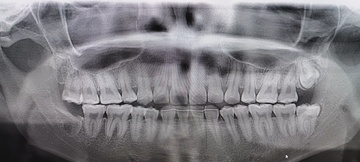

Before(下親知らずの抜歯前) 虫歯のある状態で埋まっている親知らず 抜歯前の骨の状態のレントゲン像

After(下親知らずの抜歯後) 横に生えた状態で埋まっている親知らずの抜歯後 虫歯がある親知らずの抜歯後 抜歯後の骨の状態のレントゲン像

原因をより詳しく調べるためパノラマレントゲンを撮影したところ、右下の親知らずは骨の中に埋まった状態のまま虫歯になり、隣接する歯を押しており、接触している奥歯の骨が溶けてしまっています。 そのため、右下の親知らずと隣の奥歯の間には、歯と歯ぐきの境目の溝である「歯周ポケット」が通常よりもかなり深くなっていました。

以上の点から、痛みの原因は、虫歯により深くなった歯周ポケットの中で歯垢が溜まって細菌が繁殖し、親知らず周囲の歯ぐきに炎症が起きる「智歯周囲炎」であると診断しました。

まず、親知らずと骨の中にある神経の位置、歯や周囲の骨の詳細な情報を確認するために、歯科用パノラマデジタル写真で口腔内を撮影します。撮影結果を踏まえ、抜歯方法や施術の難易度をしっかり確認しました。

1年後、取り除いた親知らず周囲の骨がしっかり再生したことを確認しました。